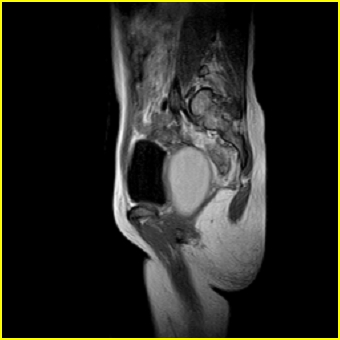

女、15岁、下腹疼痛2天,排尿困难1天。查体:处女膜闭锁,距处女膜约4至5cm处扪及一约5cm直径的圆形包块,张力较高,触痛明显、欠活动。b超提示子宫增大伴宫内增强回声团。

更正影像意见:阴道积血。

处女膜闭锁,阴道积血

处女膜闭锁,阴道积血,子宫积血.

处女膜闭锁,伴子宫及阴道积血.